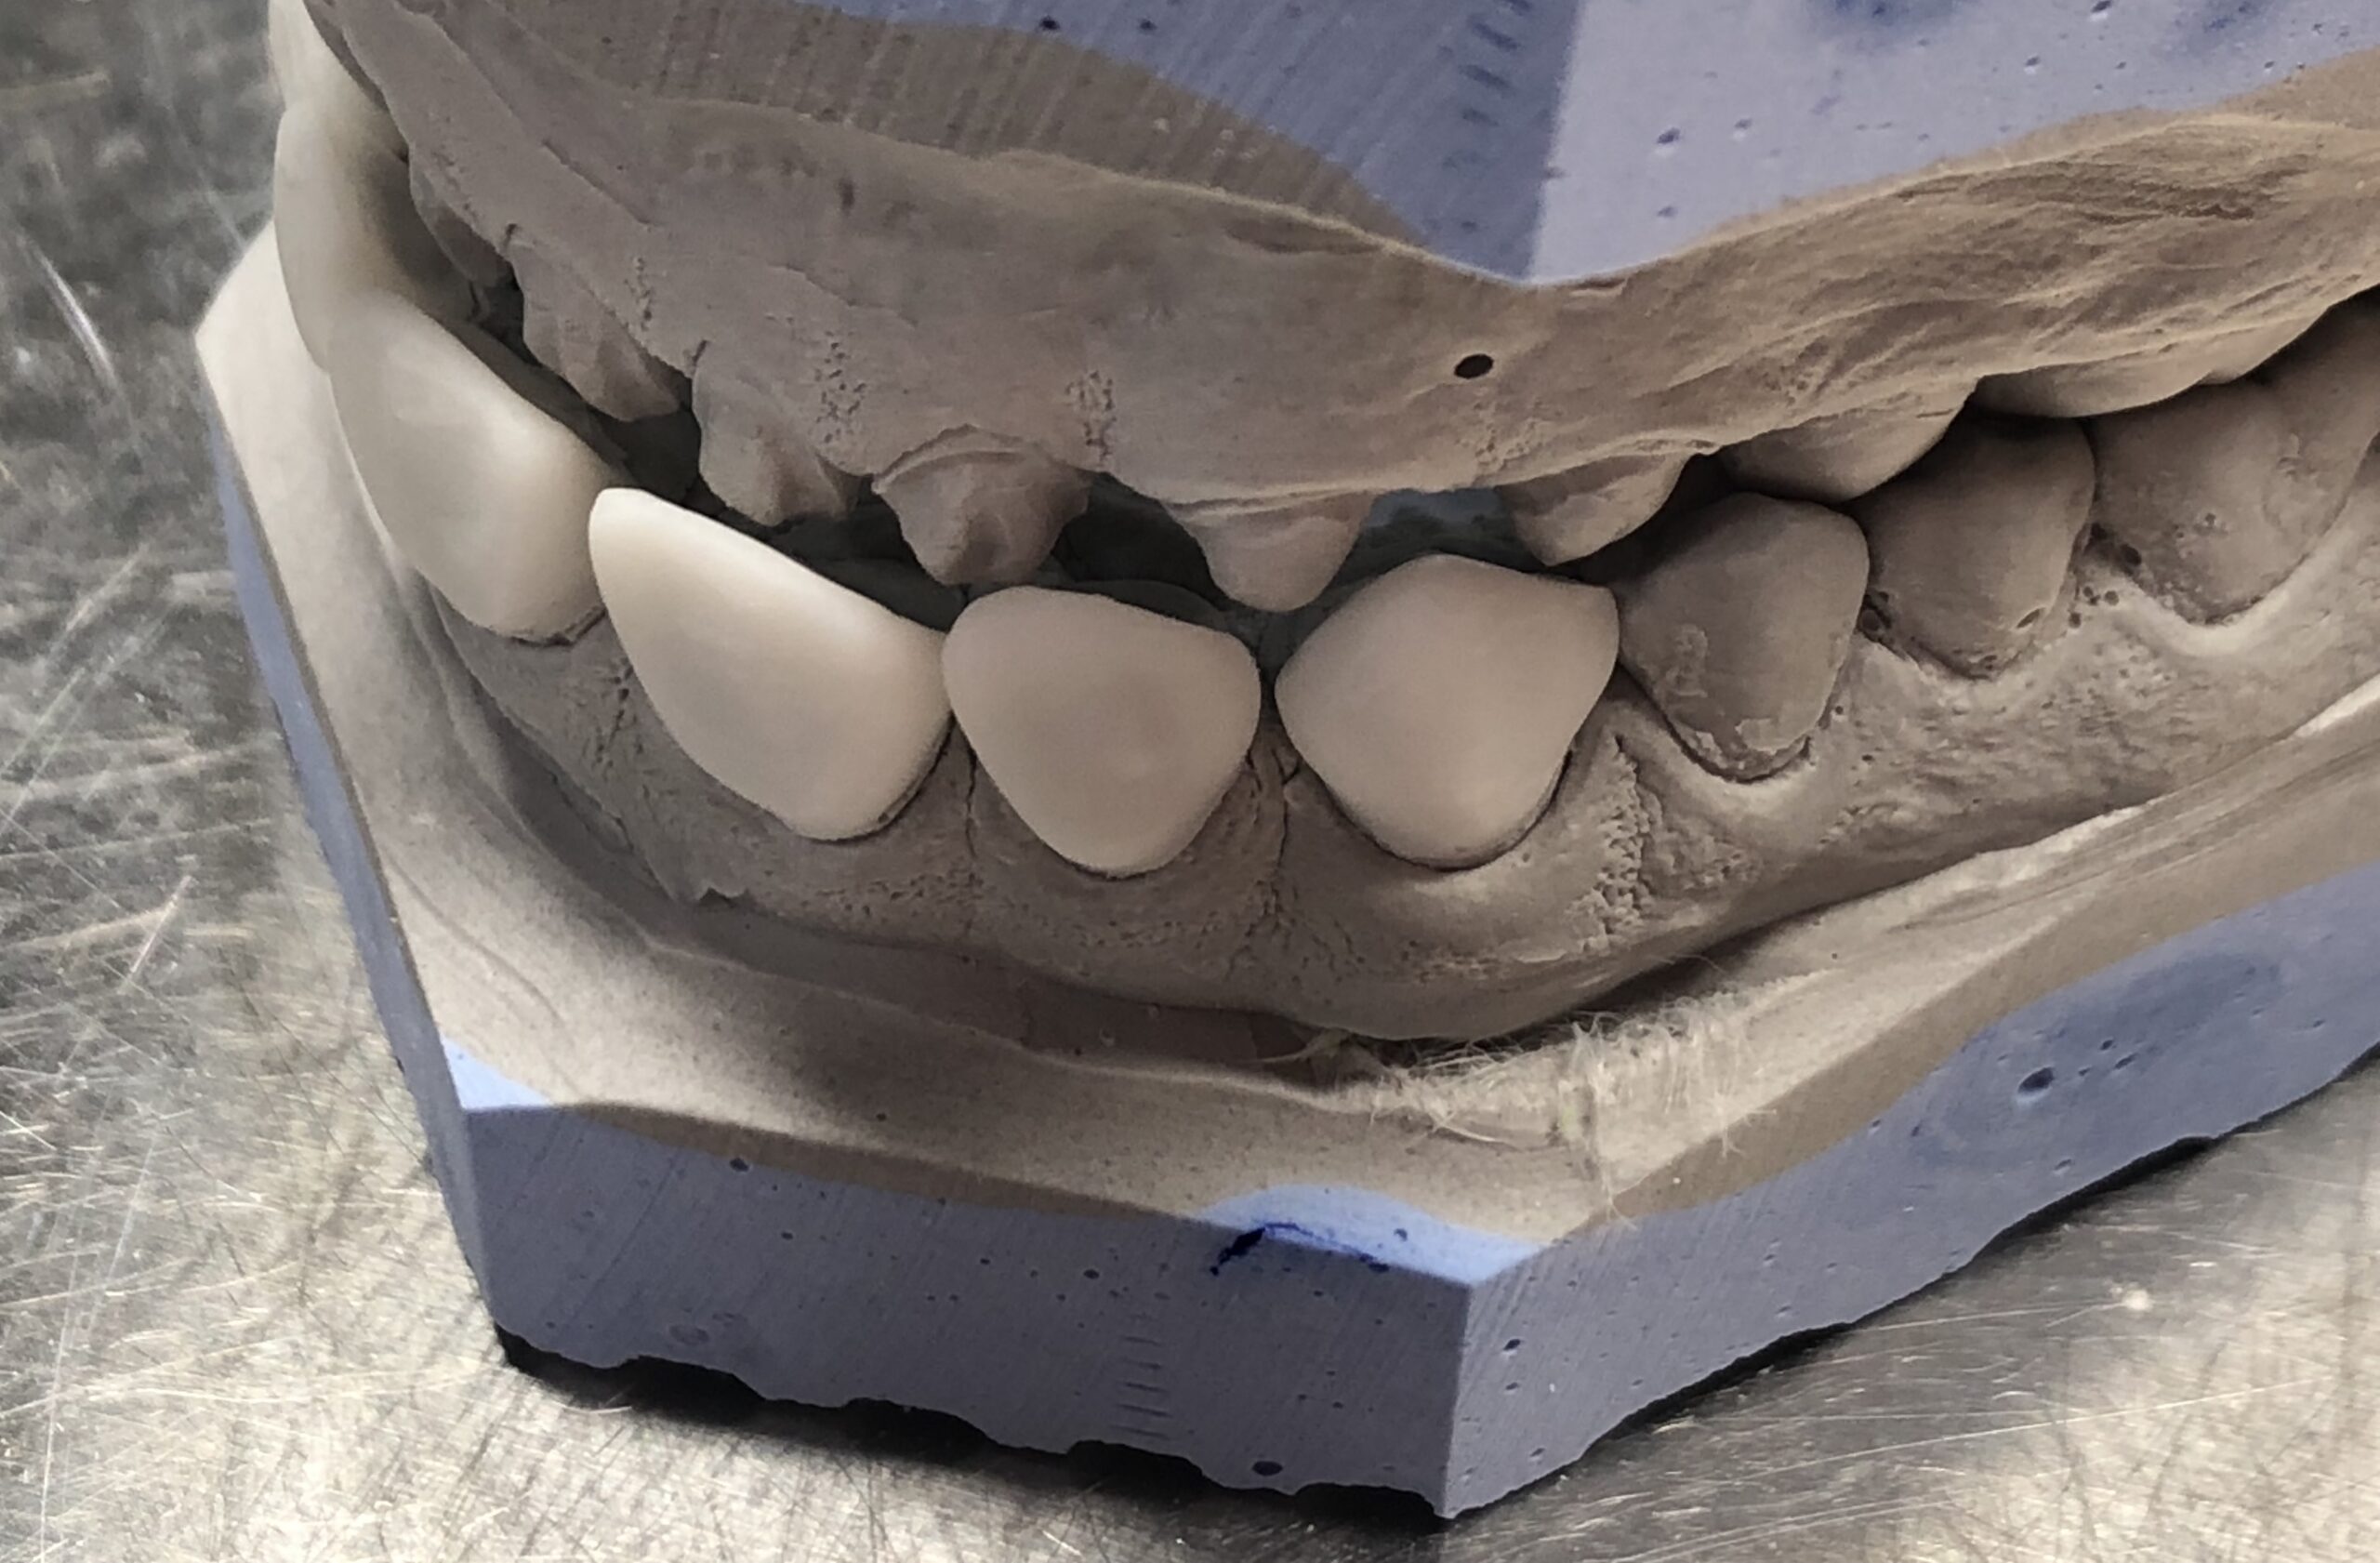

Nos réalisations : Conjointe

Céramique sur Zircone

La zircone présente une très grande résistance à la flexion (plus de 1 400 Mpa).

Translucide, elle reflète la lumière aussi naturellement que l’émail.

Biocompatible elle est garante d’une excellente intégration gingivale.